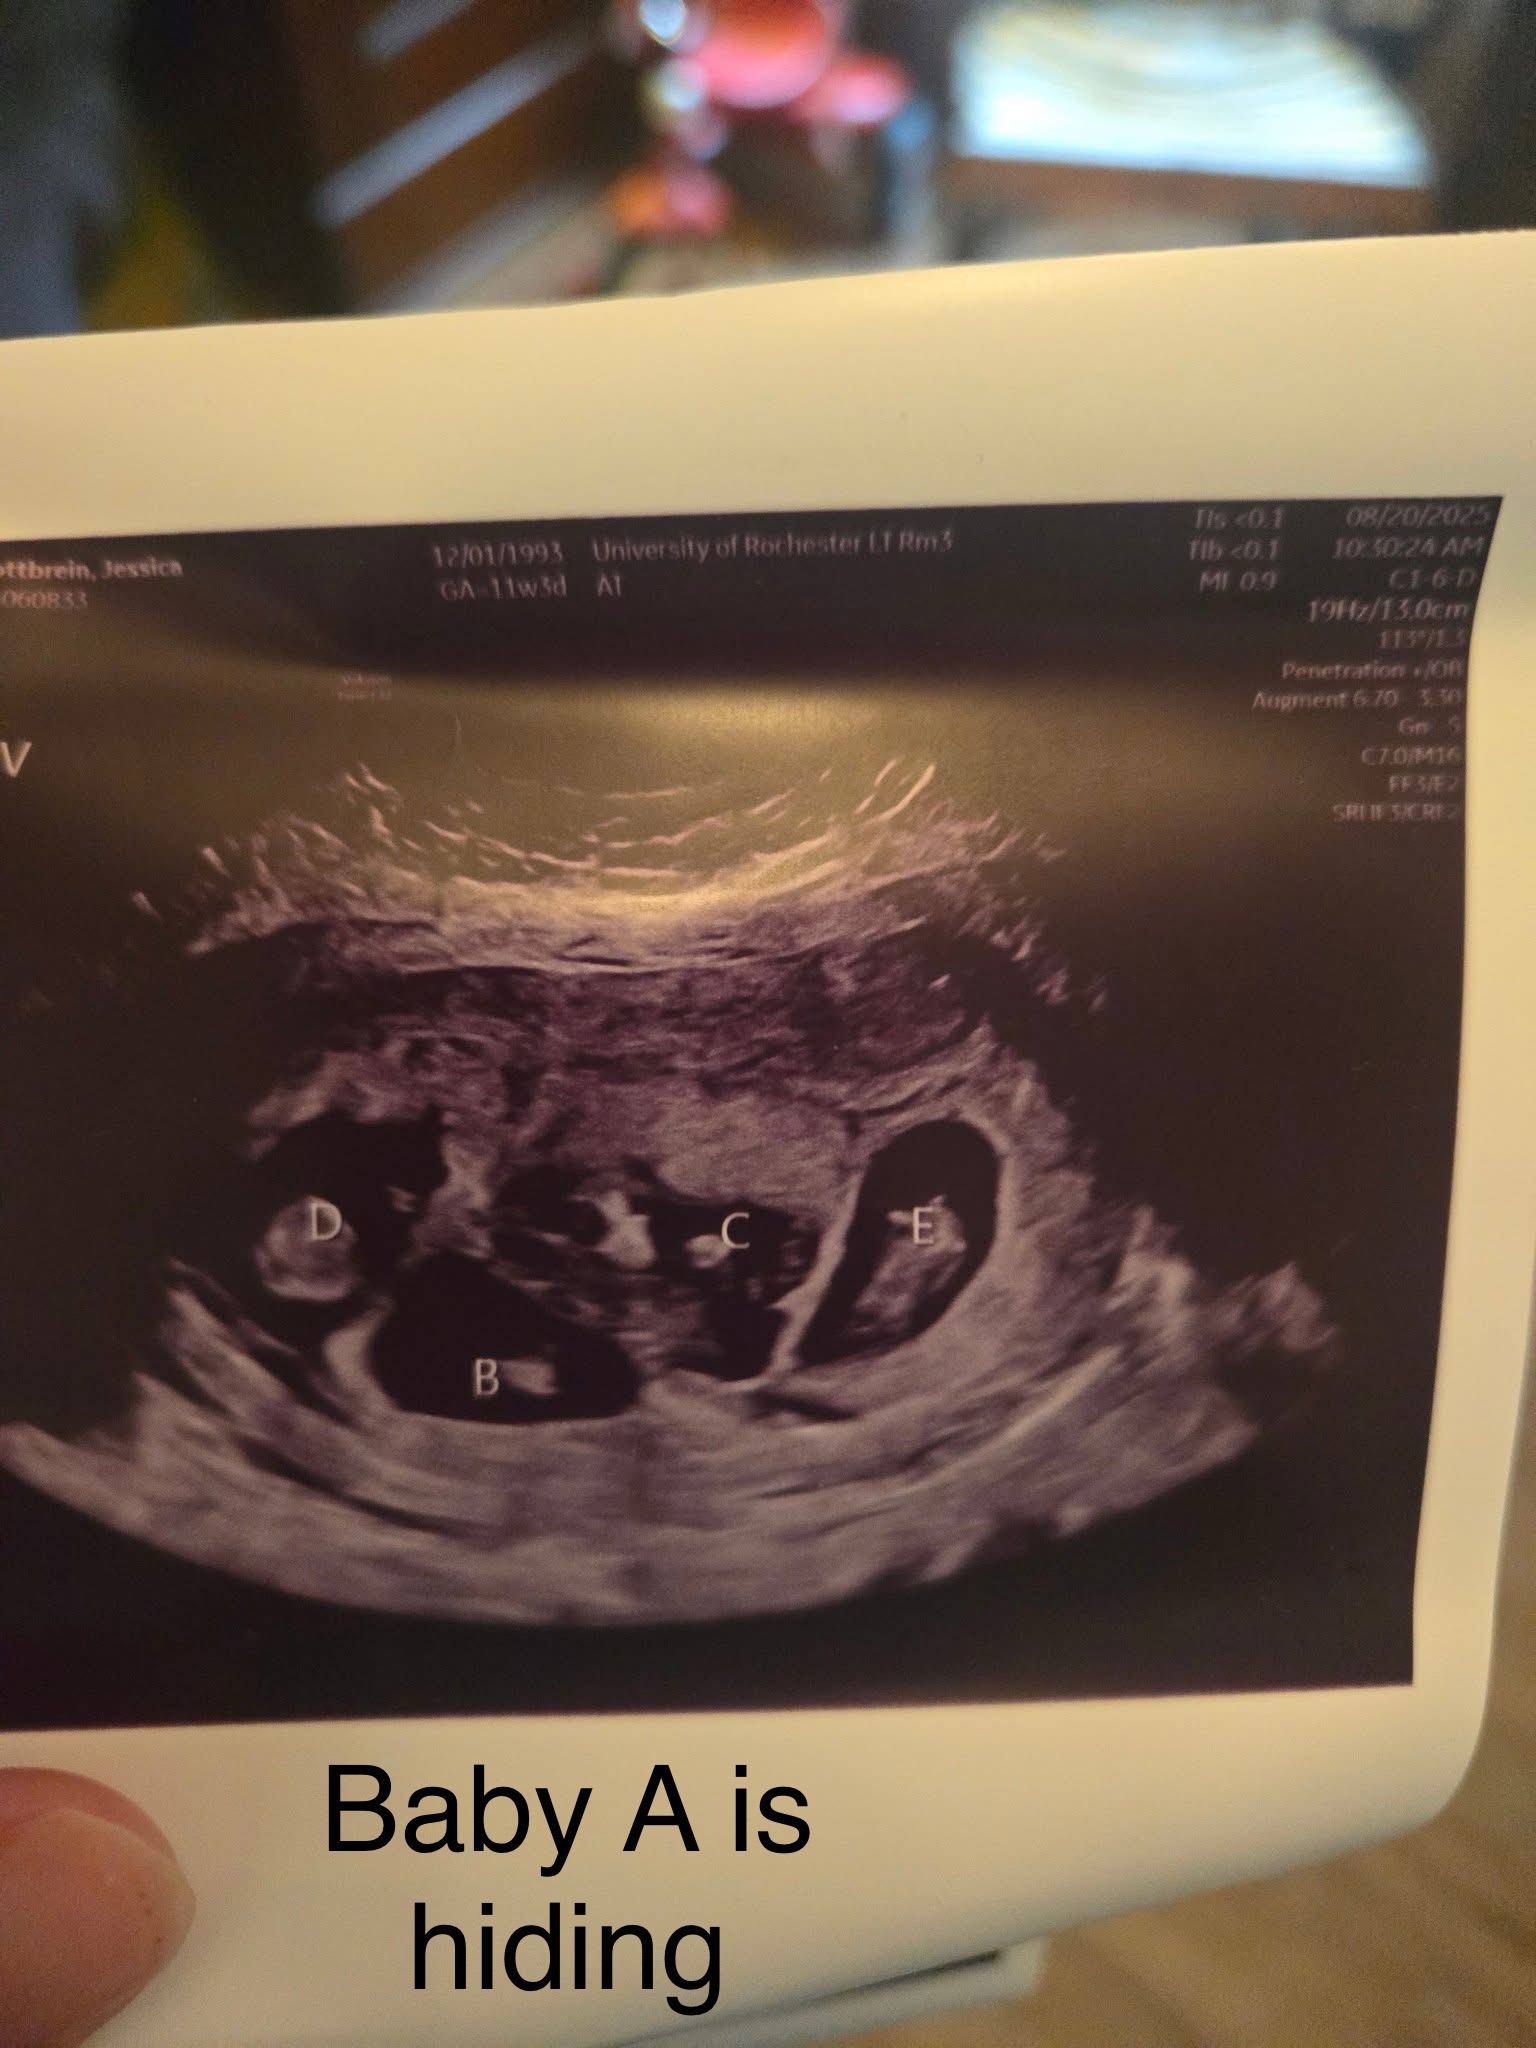

Jess is an amazing mother to her two young daughters, Hannah and Brooke, and a dedicated wife to the love of her life, John. They recently decided to expand their family and went through some fertility treatments. It was not IVF. She spontaneously released five eggs and all five were fertilized. Once again, this was not an intentional thing, nor is it something that could’ve been predicted. So now she is almost 20 weeks pregnant with quintuplets! For those of you who don’t know, that is five babies tucked safely away in her belly. The babies are thriving; they’re growing at appropriate rates, and as of right now, there’s no sign of major complications.